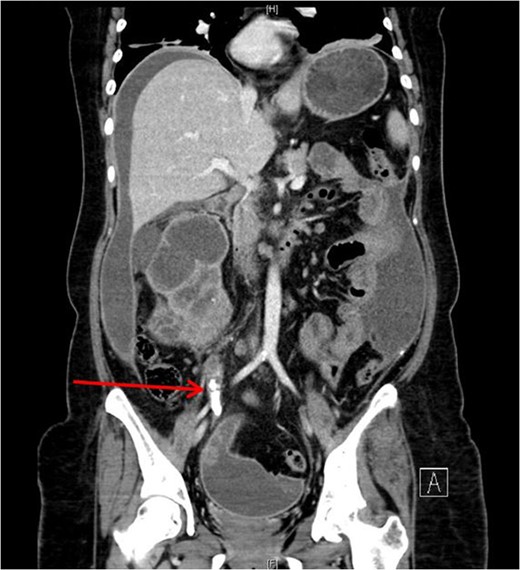

She underwent insertion of a right percutaneous nephrostomy drain, percutaneous drainage of the anterior abdominal collection, as well as a percutaneous biopsy of the right renal soft tissue lesion. Urine cultures from the percutaneous nephrostomy grew Proteus mirabilis. Fluid cytology from the abdominal collection showed acute inflammatory cells. Biopsy of the renal lesion showed xanthogranulomatous inflammation.

After a period of antibiotic treatment, she underwent open right nephroureterectomy with exploration, drainage and washout of the preperitoneal collection. During surgery, 1 l of pus was drained from the preperitoneal space, and cultures grew P. mirabilis. The ureter was ligated below the level of the calculus and removed together with the kidney. Final histopathology results showed XGPN with no evidence of malignancy in the kidney or peritoneal lining.

Our patient had an atypical presentation with abdominal distension and presumed ascites, which was eventually revealed to be an anterior preperitoneal collection secondary to infection. Although the initial suspicion was that of a malignant process complicated by ascites, subsequent cytology and histopathological results showed that it was likely benign. In view of the non-functioning renal unit and significant abdominal collection, she underwent definitive surgery.

The most common urinary pathogen identified was Escherichiacoli [3], and common areas of involvement were the retroperitoneum and psoas muscle. In our patient, the retroperitoneal space was surprisingly not greatly involved, but rather it was the anterior preperitoneal space that had significant adhesions and inflammation. The pathogen identified from both nephrostomy and preperitoneal collection was P. mirabilis, showing that both pathologies were linked.